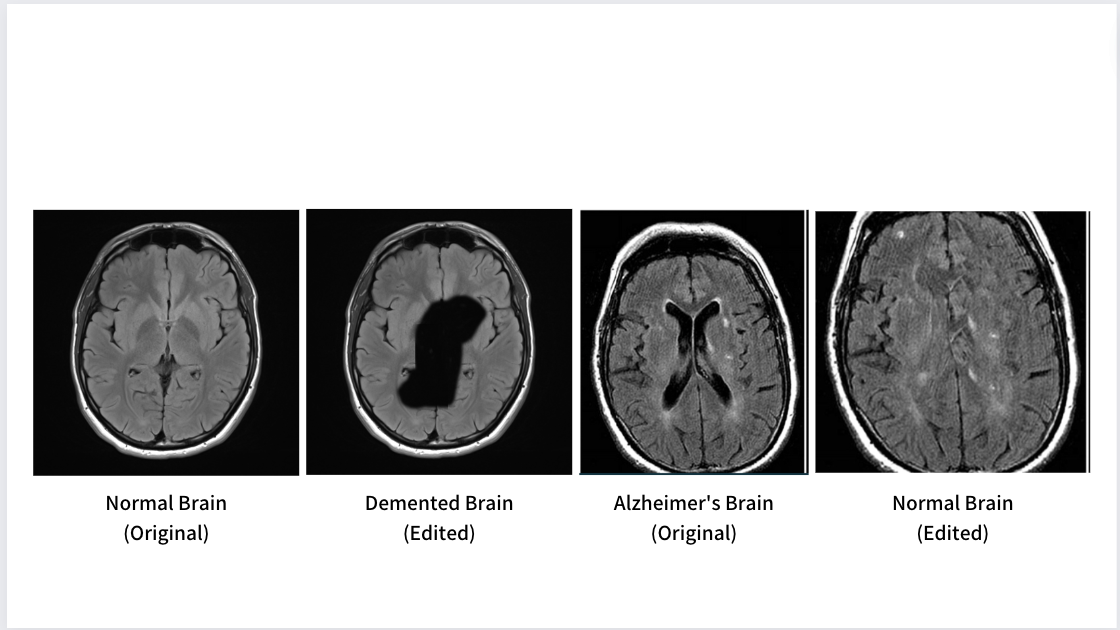

Alzhiemer's MRI Classification

Convolutional Neural Networks, Machine Learning / March 2023